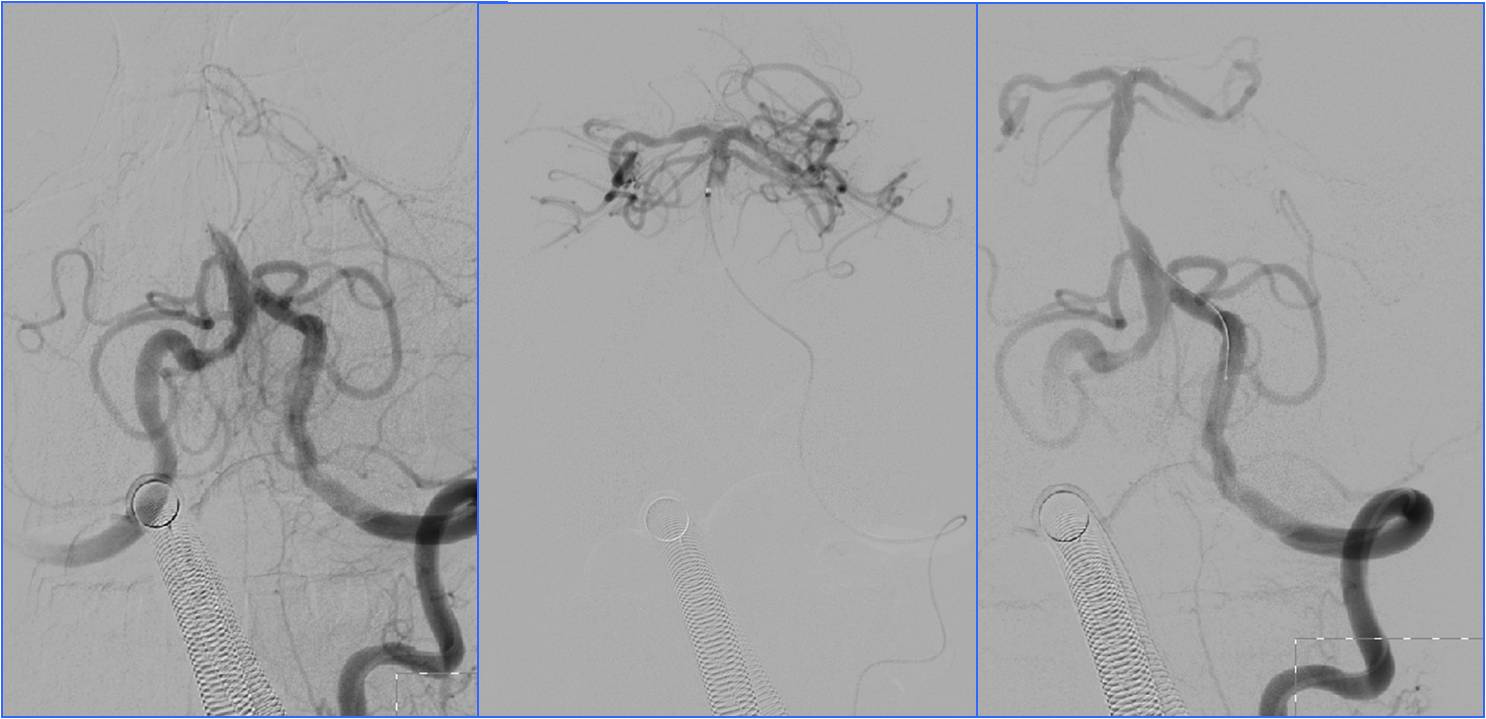

》13:22进入导管室行血管内治疗。行气管插管全身麻醉。

》DSA见基底动脉闭塞,Solitaire支架取栓后见基底动脉重度狭窄,Gateway球囊扩张,置入Wingspan支架。

▼13:49DSA

▼支架取栓后基底动脉残余重度狭窄

▼基底动脉支架置入术

▼4天后复查MRA